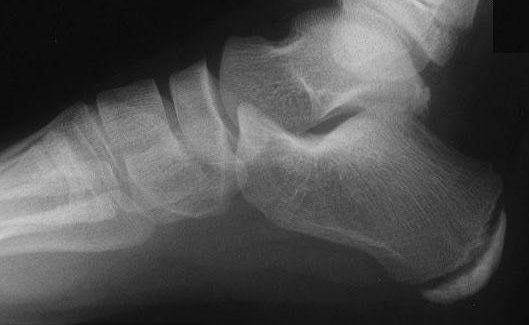

Xray of a Child's Foot

Xray of a Adults Foot